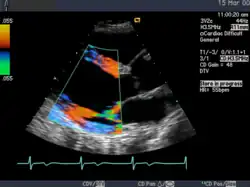

Die Aussagekraft der Sonografie kann erheblich durch die Anwendung des Doppler-Effekts erhöht werden. Man unterscheidet eindimensionale Verfahren (Pulsed-Wave-Doppler, Continuous-Wave-Doppler, auch als D-mode bezeichnet) von zweidimensionalen, farbkodierten Anwendungen (Farbdoppler – F-mode). Die Kombination B-Bild mit Pulsed-Wave-Doppler (PW-Doppler) nennt man auch Duplex.[4]

Doppler-Verfahren werden benutzt zur Bestimmung von Blutfluss-Geschwindigkeiten, zur Entdeckung und Beurteilung von Herz(klappen)fehlern, Verengungen (Stenosen), Verschlüssen oder Kurzschlussverbindungen (Shunts), siehe Farbkodierte Doppler-Sonografie.

Bei der farbkodierten Doppler-Sonografie wird für einen großen Bereich eines konventionellen Ultraschallbildes (Color-Window) die örtliche Doppler-Frequenz (= mittlere Flussgeschwindigkeit) und deren Schwankungsbreite bestimmt. Damit möchte man die Turbulenz der Strömung abschätzen. Aufgrund der statistischen Bewegungen der Streuteilchen ist die Schwankungsbreite der Fließgeschwindigkeit jedoch stets größer als die Turbulenz. Das Ergebnis wird in Falschfarben auf dem B-Bild überlagert, also in Farbtönen von rot und blau für verschiedene Blutgeschwindigkeit und grün für Turbulenz. Hierbei steht üblicherweise die Farbe Rot für Bewegung auf den Schallkopf zu, während mit blauen Farbtönen Flüsse weg von der Sonde codiert werden. Bereiche der Geschwindigkeit 0 werden durch die Elektronik unterdrückt.

Anwendung des Doppler-Verfahrens bei einer Herzuntersuchung: Mitralklappeninsuffizienz -